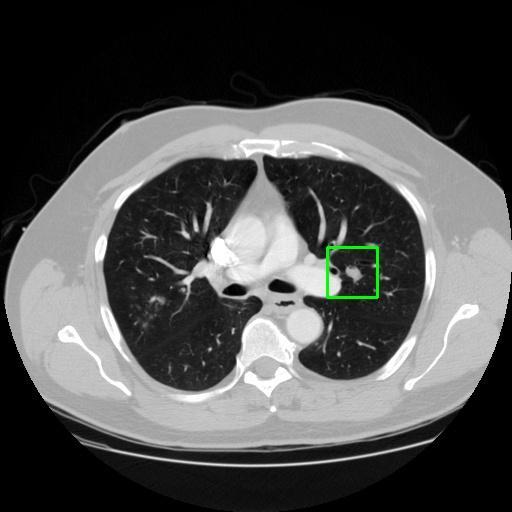

We developed an AI-based system using deep learning models for analyzing lung CT scans to detect and classify pulmonary nodules. We chose the YOLOv11 architecture for its enhanced object detection capability and adapted it specifically for medical imaging, incorporating pixel-level precision and severity classification.

Classification into three severity levels with colored bounding boxes.

Achieved ~0.90 mAP@0.5 on validation data, showing strong object detection capabilities even on complex medical images.

Designed a severity classification system that categorizes nodules into null, moderate, and severe using colored bounding boxes, assisting in rapid clinical decision-making.